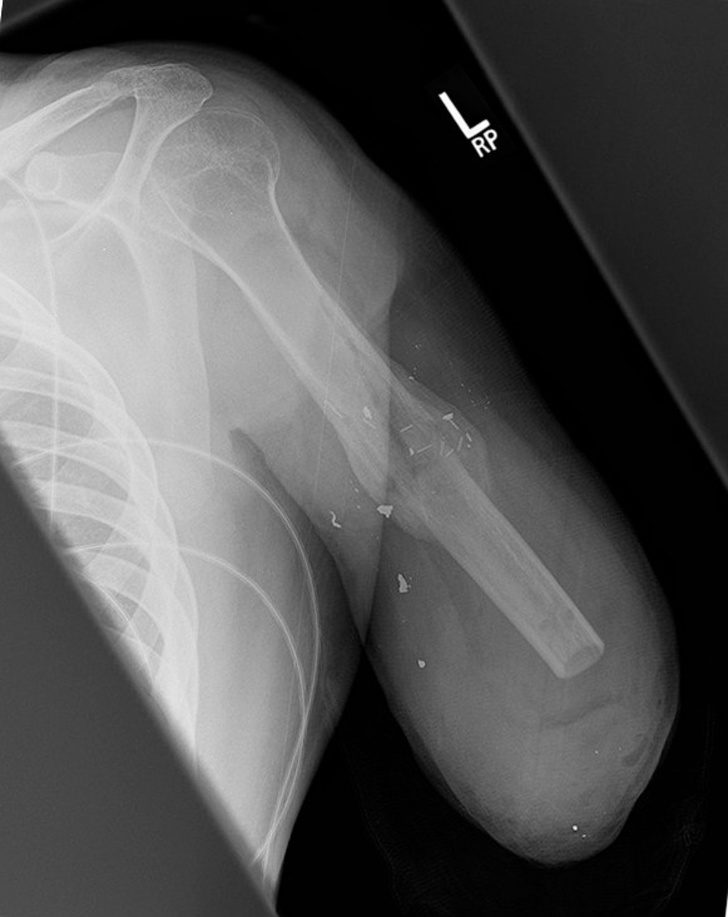

13. Так на рентгене выглядит рука после ампутации